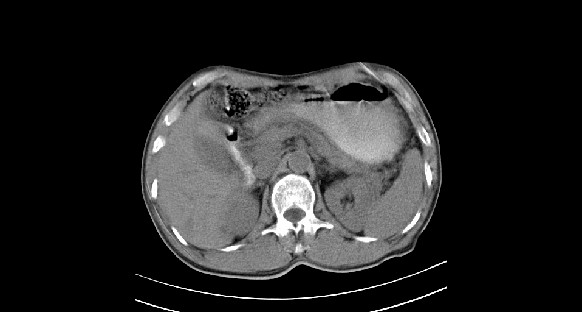

男性,70岁,体检b超发现左肾占位,请各位战友发表一下观点

左肾有两个病灶,且较大的病灶内可见点状钙化灶,增强扫描边缘也是呈渐进性强化,中央部分未见明显强化